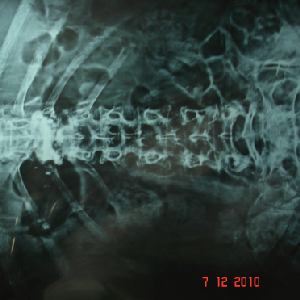

Double cord syndrome – DIASTOMATOMYELIA – is a very rare entity, wherein patient

is having congenital deformity of spine with separation of the spinal cord into

two halves by a bony or fibrous septum It is a great challenge to operate these

pts as , if something goes wrong, pt would become paraplegic for her life time.

Perticularly, in this case, as pt was only 9 years old and having congenital deformity

of the vertebrae, it was corrected simultaneously at Sola civil hospital - ahmedabad.